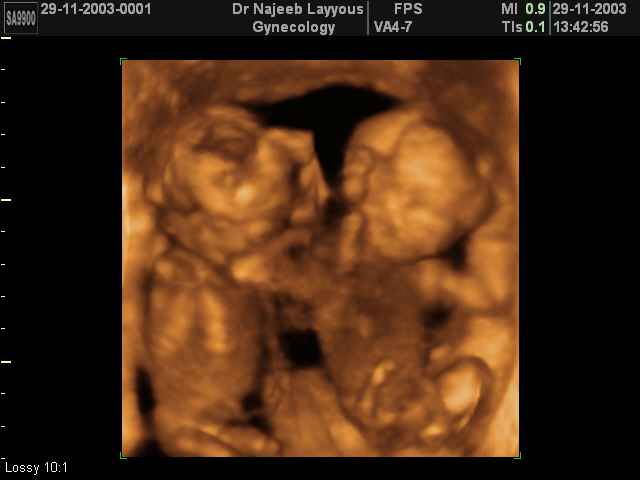

اجنة توام عمرهم 11 اسبوع

شوفوا هذول واحد يدف اخوه يا حلوهم